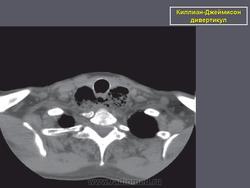

Киллиан – Джеймисон - дивертикул

Киллиан – Джеймисон - дивертикул.

Приложения:

0.radiographics_logo.png0.rg_.337125153.fig15advustoronnyaya_killian-dzhemison_divertikulov_v_76-letney_zhenshchiny.gif0.rg_.337125153.fig15bdvustoronnyaya_killian-dzhemison_divertikulov_v_76-letney_zhenshchiny.gif